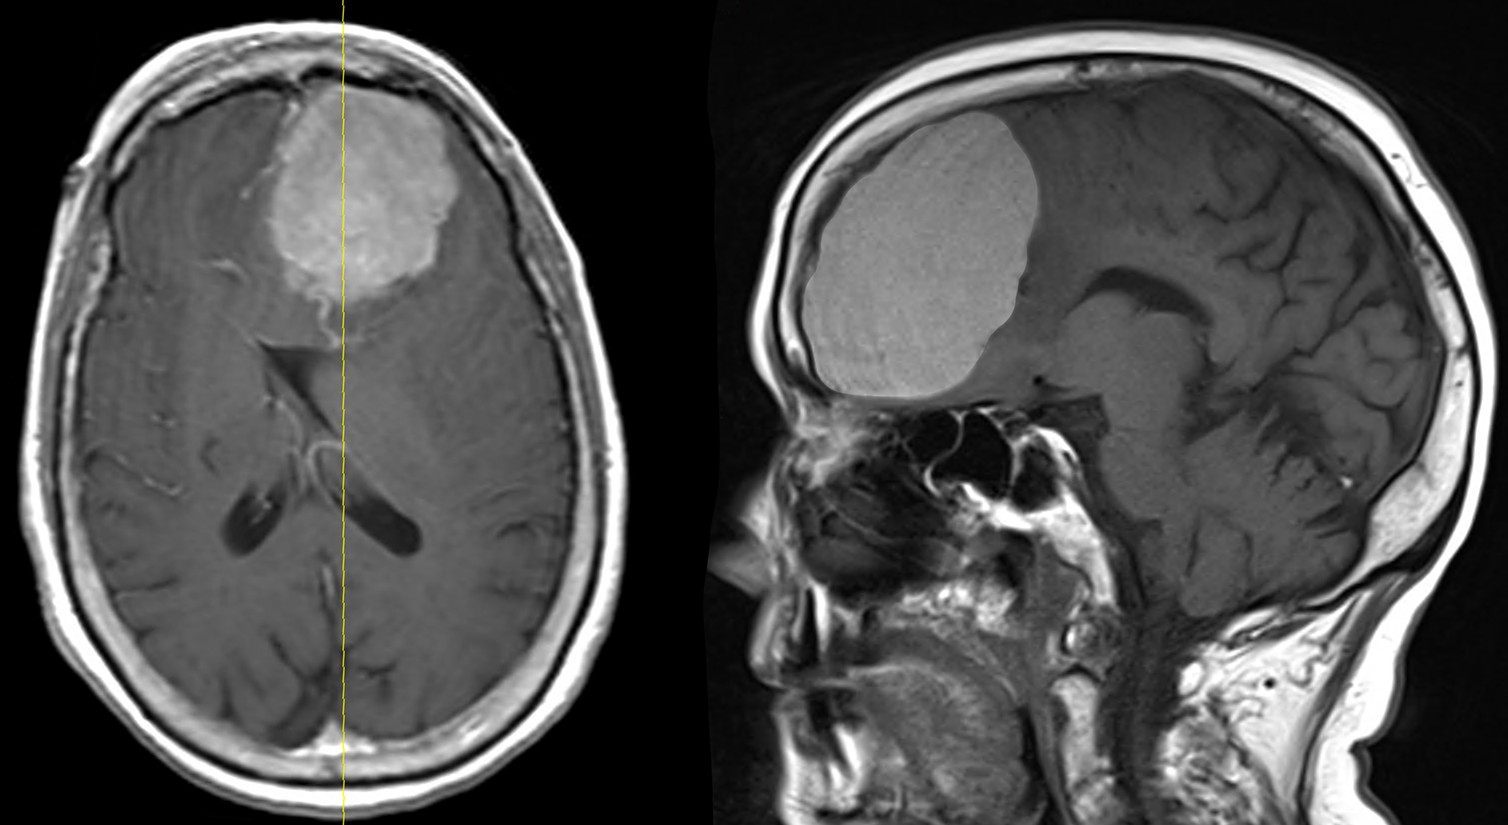

6. Chẩn đoán u màng não

U màng não hiếm khi được phát hiện sớm trước khi xuất hiện triệu chứng.

Nếu có dấu hiệu nghi ngờ khối u, bác sĩ có thể chỉ định chụp MRI và/hoặc CT scan để xác định vị trí và kích thước của khối u.

Trong một số trường hợp, bác sĩ có thể tiến hành sinh thiết. Phẫu thuật viên sẽ lấy một phần hoặc toàn bộ khối u để kiểm tra xem đó là khối u lành tính hay ác tính.

MRI có thể xác định u màng não là lành tính hay ác tính không?

Chụp MRI và CT scan có thể giúp phân biệt u màng não lành tính hay ác tính. Tuy nhiên, sinh thiết phẫu thuật vẫn là phương pháp chính xác nhất để xác định bản chất của khối u.